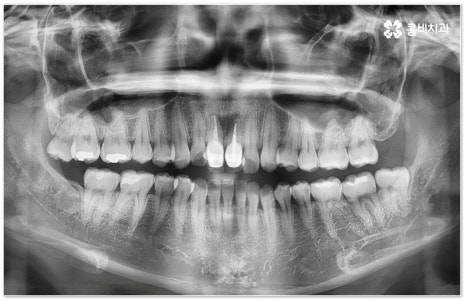

희고 가지런한 치아를 드러내며 환하게 웃는 사람을 보면 자기도 모르게 호감이 가곤하죠, 이처럼 대인 관계에서 치아는 좋은 인상을 만드는 데 심미적으로 큰 역할을 할 뿐 아니라 식사시 음식물을 저작하고 발음을 제대로 하는 데도 많은 도움을 주기 때문에 만약 타고난 치아가 삐뚤어졌거나 위아래 교합이 제대로 맞지 않는다면 이를 기능적 심미적으로 바로잡아 주기 위해서 치아 교정 치료를 고려해 볼 수 있습니다.

이때 환자분들의 상황에 따라서 구조적인 원인이 크지 않고 교합이 심하게 어긋나지 않은 상태에서 치아의 각도만 살짝 앞으로 튀어나와 있거나 사이가 조금 벌어져 있는 등 부분 교정으로 치열을 가지런하게 바로잡을 수 있는 케이스도 있는데 이런 경우 6~8개월 정도의 보다 짧은 기간에 간편하게 치료를 끝낼 수 있으니 먼저 꼼꼼한 검진을 통해 자신이 부분 교정이 가능한지 여부를 알아보시면 좋을 거예요.

부정교합을 개선할 때 교합이 어긋난 정도가 심하고 구조적인 원인이 커서 부분 교정이 아닌 전체 교정이 필요한 케이스인 경우라고 해도 말씀드렸던 클리피씨 교정 장치 또는 보다 심미성을 강조한 치아교정장치 들의 도움을 통해 다른 사람과 얘기를 하거나 음식을 먹을 때 브라켓이 두드러지게 드러나는 부담을 줄일 수 있으니 설측교정, 콤비교정, 투명교정, 인비절라인 등에 대해서 한 번 알아보시고 각자에게 맞는 방법으로 교정 치료를 시작해 보시길 권유드리고 있어요.

적지 않은 치아교정 비용 역시 치료 시작을 망설이시는 이유가 될 수 있는데요. 그렇다고 해서 치과를 선택할 때 가격적인 메리트만 생각하시기 보다는 교정 치료의 목적이 앞으로 남은 평생 동안 건강하게 사용해야 할 치아의 기능적 심미적인 개선에 있는 만큼 해당 임상 분야의 경험이 풍부하고 뛰어난 노하우를 가지고 있는 의료진과 함께 하는데 초점을 맞추시길 당부드리고 있어요. 또한 처음부터 끝까지 책임 진료하고 사후 관리 역시 철저하게 케어되는 곳인지, 3D CT와 같은 정밀 검진 장비를 갖추고 있는 곳인지 여부도 중요하기 때문에 이런 부분도 함께 살펴보시면 좋을 거예요. 환자 개개인에 맞춤 치료 계획을 세워 무리하지 않은 치아 이동을 통해 전체 구강 건강을 증진시키는 방향으로 교정 치료를 하기 위해서는 이와 같이 의료진의 숙련도 외에도 케어 시스템이나 장비 같은 부분을 꼼꼼하게 체크해 보시는 것이 치과를 선택하는 데 도움이 될 수 있습니다.